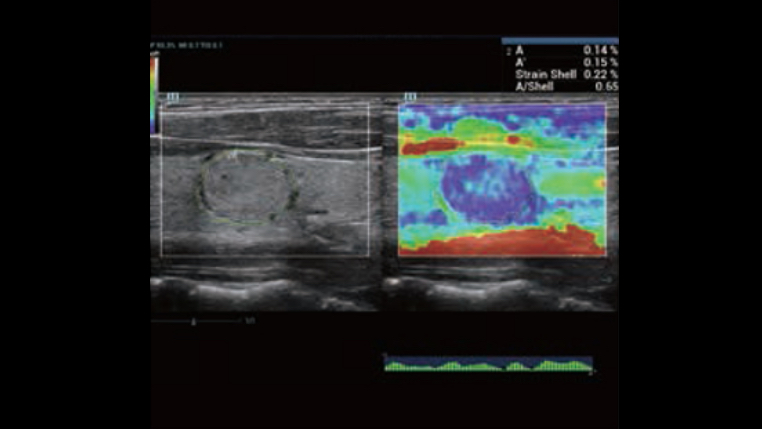

Channel data based ZST+ provides Enhanced Channel Data Processing for greatly improved imaging clarity. By multiple and retrospective channel data processing, it makes the best use of acoustic information for image improvement.

HD Scope: By processing channel data retrospectively, HD Scope enables tissue-specific enhancement with improved detailed information and image contrast on specific region of interest.